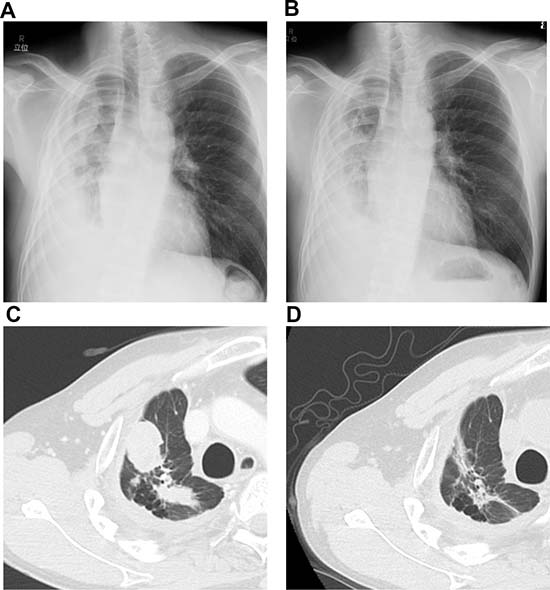

A 40-year-old Japanese man presented to our hospital with pulmonary adenocarcinoma. He had been diagnosed with adenocarcinoma 2 years ago, and RNA sequencing revealed the presence of the EML4-ALK fusion protein. When he was diagnosed, he rejected all our recommendations for chemotherapy including ALK-TKI and he stopped his annual visits to our clinic. Six months after the initial diagnosis, he presented to our hospital with dyspnea due to cardiac tamponade and pleural effusion. He received pericardiocentesis and thoracentesis, and he agreed to start crizotinib treatment (250 mg, twice daily). One month after the initiation of crizotinib, a computed tomography (CT) scan showed decreased pleural and pericardial effusion and shrinkage of the primary lesion. Ten months after the initiation of crizotinib, progressive disease (PD) was detected considering the enlargement of the primary lesion. Therefore, alectinib (300 mg, twice daily) was administered as second-line treatment, and a CT scan showed a partial response. Fourteen months after the initiation of alectinib, PD was detected again as an enlargement of the primary lesion. We continued alectinib until ceritinib was launched in Japan. One month after the PD detection, we switched to ceritinib (750 mg once daily) and the CT scan showed a partial response (Figure 1). Ten days after initiating ceritinib, palpable purpura was observed (Figure 2). The test results for myeloperoxidase-anti-neutrophil cytoplasmic antibody (MPO-ANCA) and proteinase 3 anti-neutrophil cytoplasmic antibody (PR3-ANCA) were negative. Skin biopsy showed LCV (Figure 3A–3B). IgA deposition was negative. Because ceritinib was the only drug we started one month before the onset of LCV, we suspected this was associated with ceritinib. We recommended withdrawal of ceritinib to the patient, however, he rejected it and therefore we continued ceritinib for another month. During this period, the purpura gradually improved, although, the patient caught a common cold and proteinuria was observed. We could not continue the drug as the patient was at risk for developing kidney vasculitis and he agreed. We therefore withdrew only ceritinib until the purpura improved. Four weeks after withdrawal, we confirmed the disappearance of the purpura and performed a rechallenge with ceritinib at the usual dose (750 mg once daily) without using any immunosuppressants. Although slight re-exacerbation of purpura was observed, it disappeared quickly, and the tumor response was maintained for 9 months after the rechallenge. Now he has been receiving carboplatin (area under the concentration-time curve 5), pemetrexed (500 mg/m2) and bevacizumab (15 mg/kg) therapy without relapse of LCV.

Figure 1: (A, C) Chest radiograph and computed tomography scan before starting ceritinib. (B, D) Chest radiograph and computed tomography scan after ceritinib treatment.